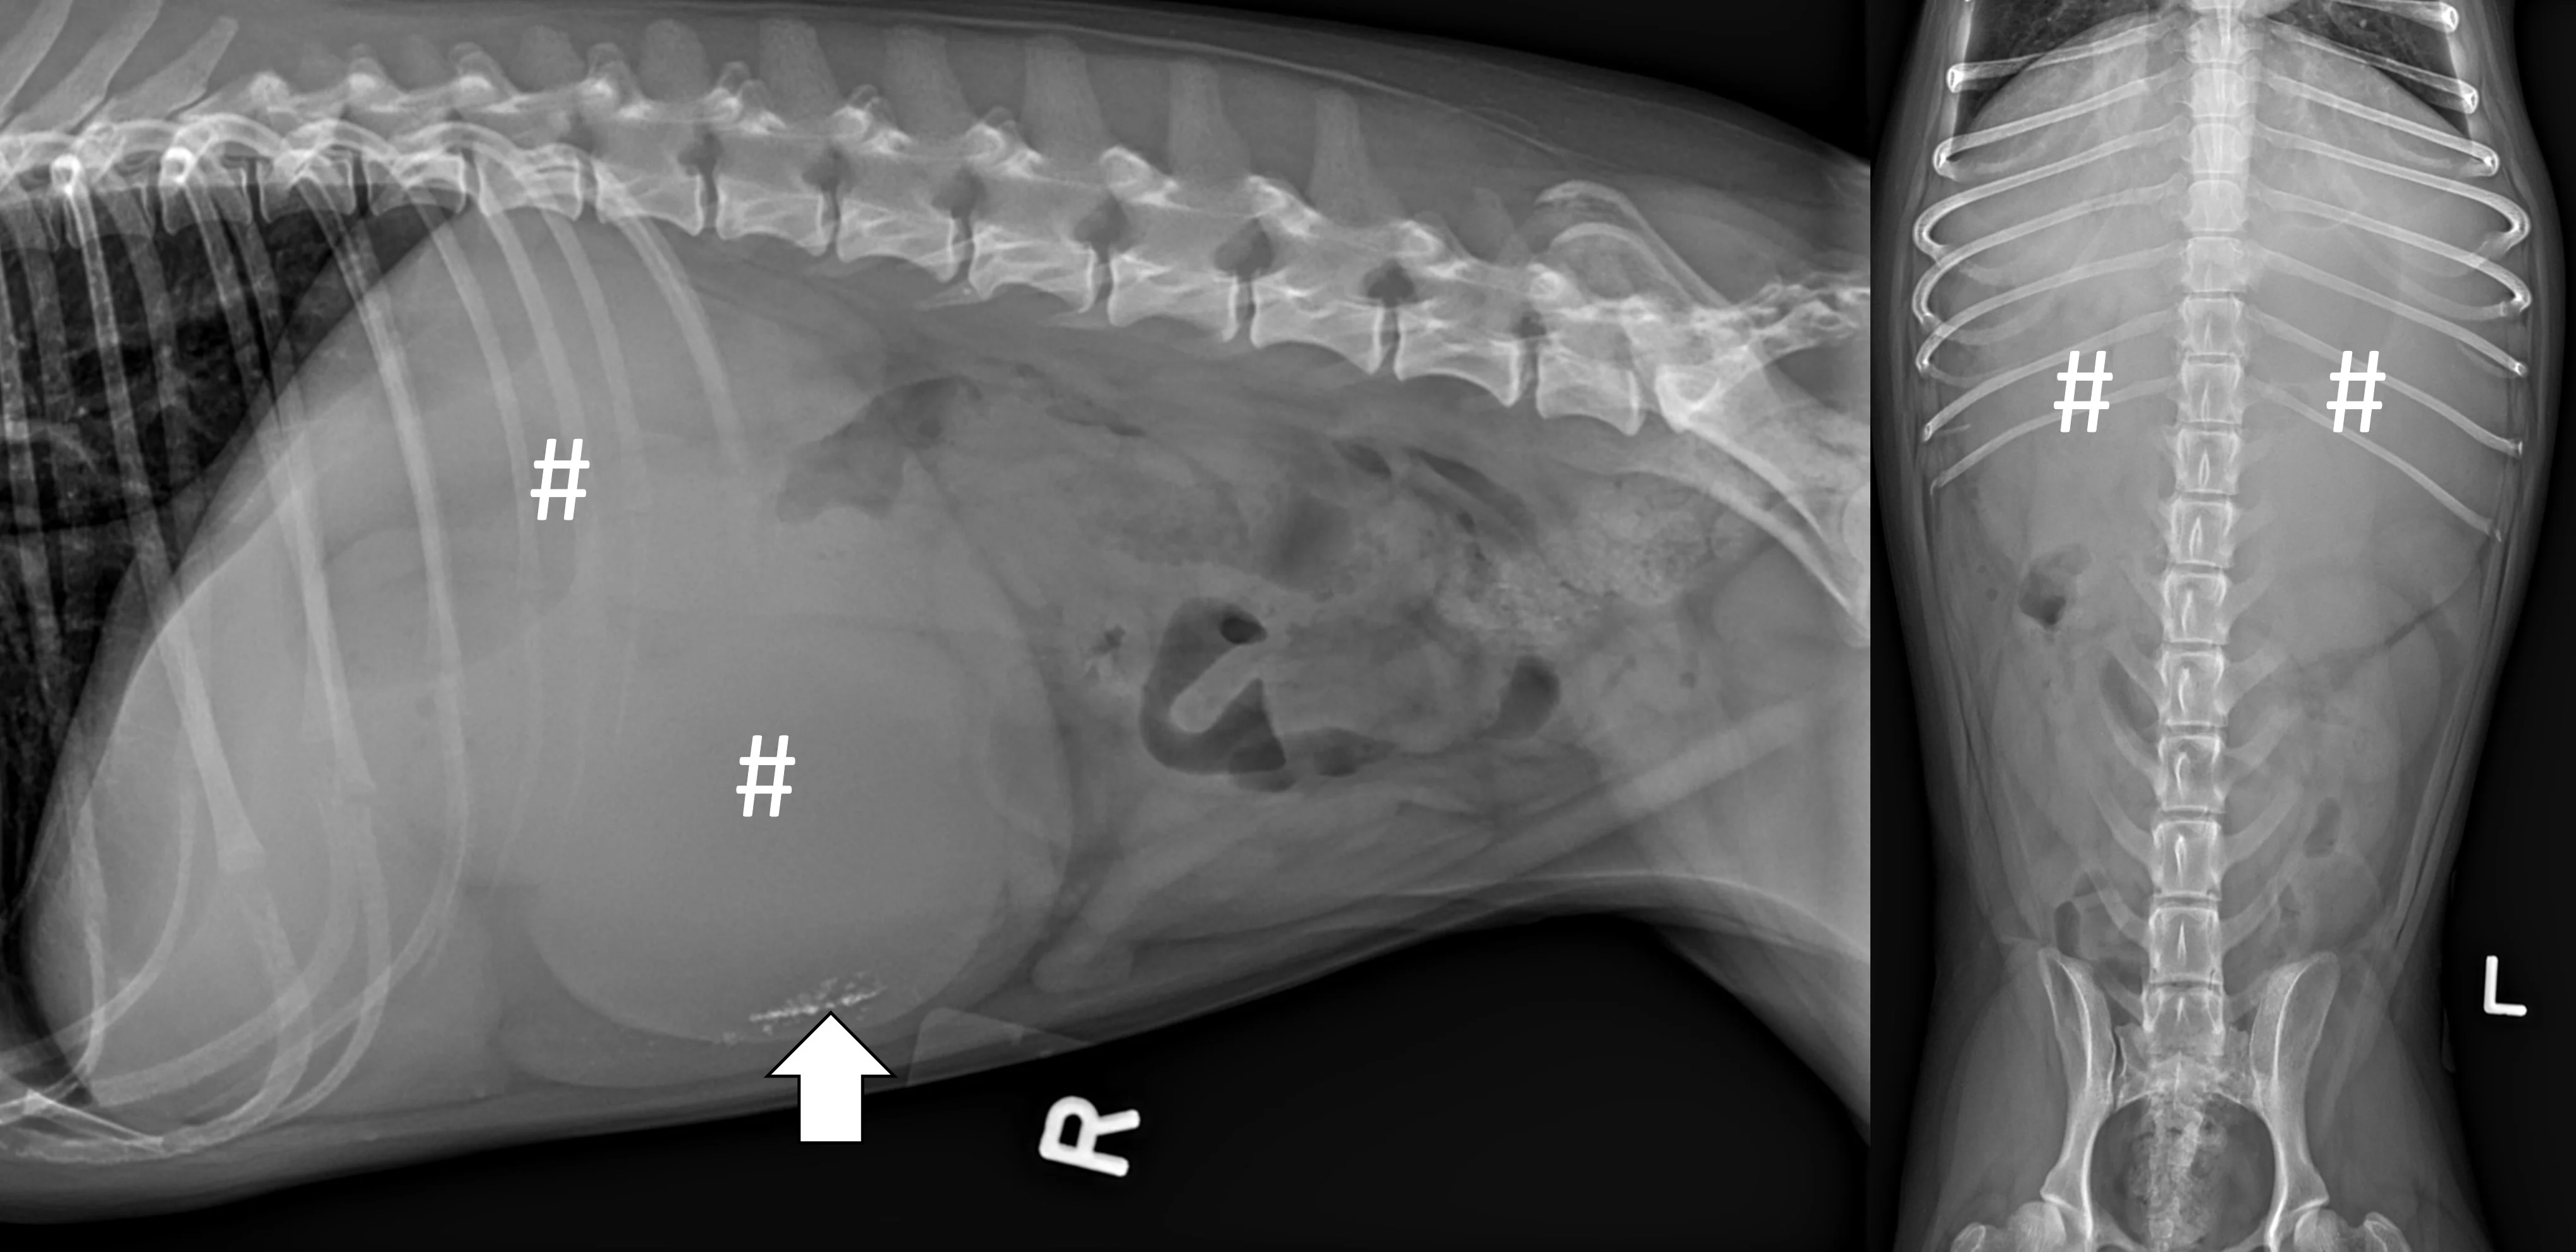

Pneumocolonogram

A pneumocolonogram can be performed to determine whether a foreign body is located in the colon or whether a focally dilated loop of intestine is part of the small bowel or colon (Figure 7).11 Sedation is often not necessary but can be used in uncooperative patients. Room air (3 mL/kg) should be administered into the rectum with an appropriately sized and lubricated red rubber catheter and syringe. Right lateral and ventrodorsal projections should be obtained immediately. The goal is to mildly dilate the entirety of the colon to the cecum with gas without overfilling the small intestine. The dose of air may need to be repeated to effect in some patients if there is inadequate filling of the entire colon.

Ventrodorsal radiographs of a 3-year-old spayed golden retriever with a small intestinal obstruction secondary to rock ingestion. Survey radiographs revealed the rock was in the left lateral abdomen but could not help determine whether the rock was in the small bowel or the descending colon (left, arrow). Pneumocolonogram was performed to mildly dilate the colon with gas (asterisks), confirming the rock was in the small bowel (right, arrow).

Modified Pneumogastrogram

A modified pneumogastrogram can be performed if there is insufficient gas in the stomach to fill the pylorus on the left lateral projection.12 A noncaffeinated carbonated beverage (60 mL; author reduces to 30 mL in patients <11 lb [5 kg]) should be given and a left lateral projection obtained immediately (Figure 8). The beverage may be administered free choice or via syringe if the patient is unwilling to drink. A modified pneumogastrogram produces less gas compared with traditional pneumogastrogram but is usually effective and avoids the need for placing an orogastric tube.

Left lateral radiographs of a 1-year-old spayed crossbreed dog with a pyloric outflow obstruction secondary to ingestion of part of a soft tissue opaque toy bone. On survey radiographs, there was insufficient gas in the stomach to fill the pylorus on the left lateral projection, masking the foreign body (top, arrow). A modified pneumogastrogram with a carbonated beverage was performed, resulting in the foreign body being outlined by gas and easily seen (bottom, arrow).